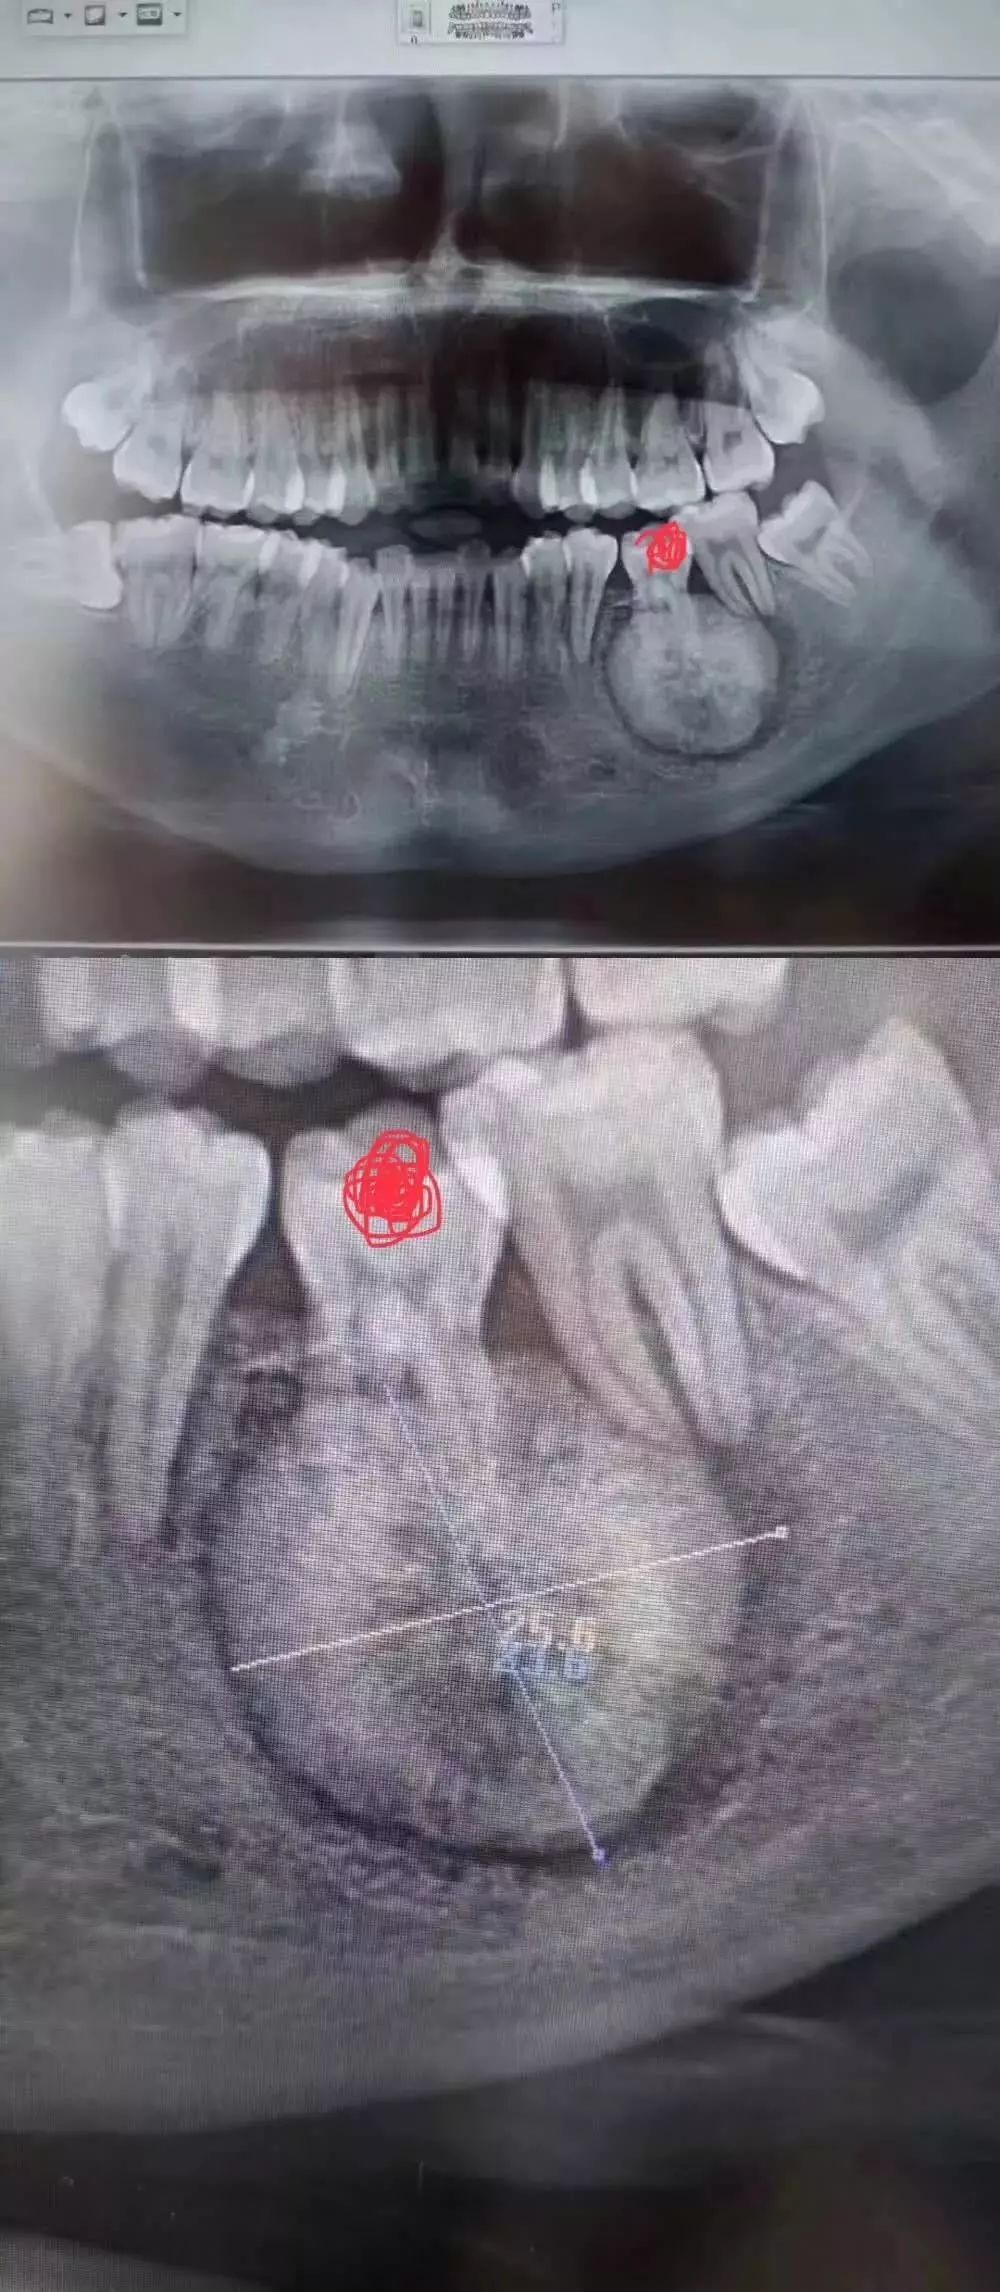

周末,小编不经意间发现一个拔牙案例刷爆了牙医们的朋友圈

相信大部分的人和小编一样,没等看到具体病情就已经被图中这个巨大的“球”状物体吓到。小小的下巴竟能长出这么大的“球”!

“患者是30多岁的年轻男子,红色标记那颗牙松动,要求拔牙,开始嫌麻烦不愿拍片,后来经过再三劝说还是拍了片。 结果把所有人包括他自己都吓了一跳。 估计是良性,具体还得去医院住院手术做病理检查,所以大家不要忽视一张片子带来辅助检查的重要性。”

试想,如果没有拍片,直接贸然拔牙,一旦出现问题......

一张牙片,“救了”诊所,也“救了”患者!